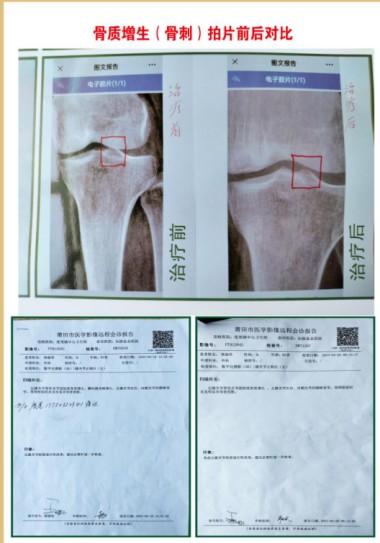

①病历依据,2012年一2016年,53岁,女,腰椎左侧弯L4,LS1。椎间隙狭窄,L3,L4,L5,LS1椎间盘向周围膨出,双侧椎间孔稍狭窄,L4,L5椎间盘积气并向周围膨出,L3,L4,L5,LS1不同程度骨质增生,走路身体变形,怕动手术风险,五年时间治疗无效,外用药水热敷配合手法操作自己治疗,22天治愈。

②病历依据,2003年一2018年依据,52岁,女,腰椎,L4,L5向椎管内突出1公分,隐窝变窄,L3,L4,5,LS1硬膜囊受压,骨质增生,走路身体三节弯歪斜,外用药水热敷,配合手法操作自己治疗,20天治愈。

③病历依据,66岁,男,生理曲度变直,椎体边缘毛糙,变尖,L3,L4,L5椎间盘膨出,L5,Ls1椎间盘向内突出,L4,L5,突出3.4㎜,椎间盘L3,L4内真空,椎间隙变窄L5,LS1,走路弯曲,外用药水热敷,配合手法操作治疗服中药15天,一个月治愈。

④病历依据,65岁,女,腰椎突出畸形L4,L5向前移位,L5椎体双侧椎弓峡部欠连续,L5,LS1椎间内真空,L5,LS1椎间隙变窄,L3,L4,L5椎间盘向后突出,相应硬膜囊受压,左侧神经根受压,椎体边缘骨质增生,外用药水热敷,配合手法操作自己治疗1个月治愈。

⑤病历依据,67岁,男,L4节向前移位,生理曲度变直,部分椎体骨质增生L4,L5,椎间盘向后偏左突出3.1㎜,硬膜囊受压,L5,LS1椎间盘向后膨出,硬膜囊受压,部分椎体积影,外用药水热敷,配合手法操作自己治疗,服中药15天治愈。

产品2015年经国家有关部门论证,其他部门评估产品为国内首创。列入2017年4月24日国务院批准成立中国510品牌日,产品正式正列入档案号:CNBZ201801978。论证单位:中国中医科学院,北京联合大学药品经营管理,北京朝阳中医院,中国中医科学院望京医院,教育部科技发展中心。本人经过多人病历报告单和拍片发现没病报告单写有病,这是治病救人,还是媒财害命。